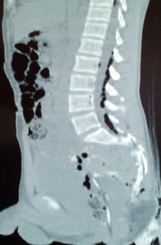

Διάταση αριστερού ουρητήρα λόγω παρουσίας πιθανής εμφύτευσης (Ευγενική παραχώρηση Dr. V. Penopoulos)